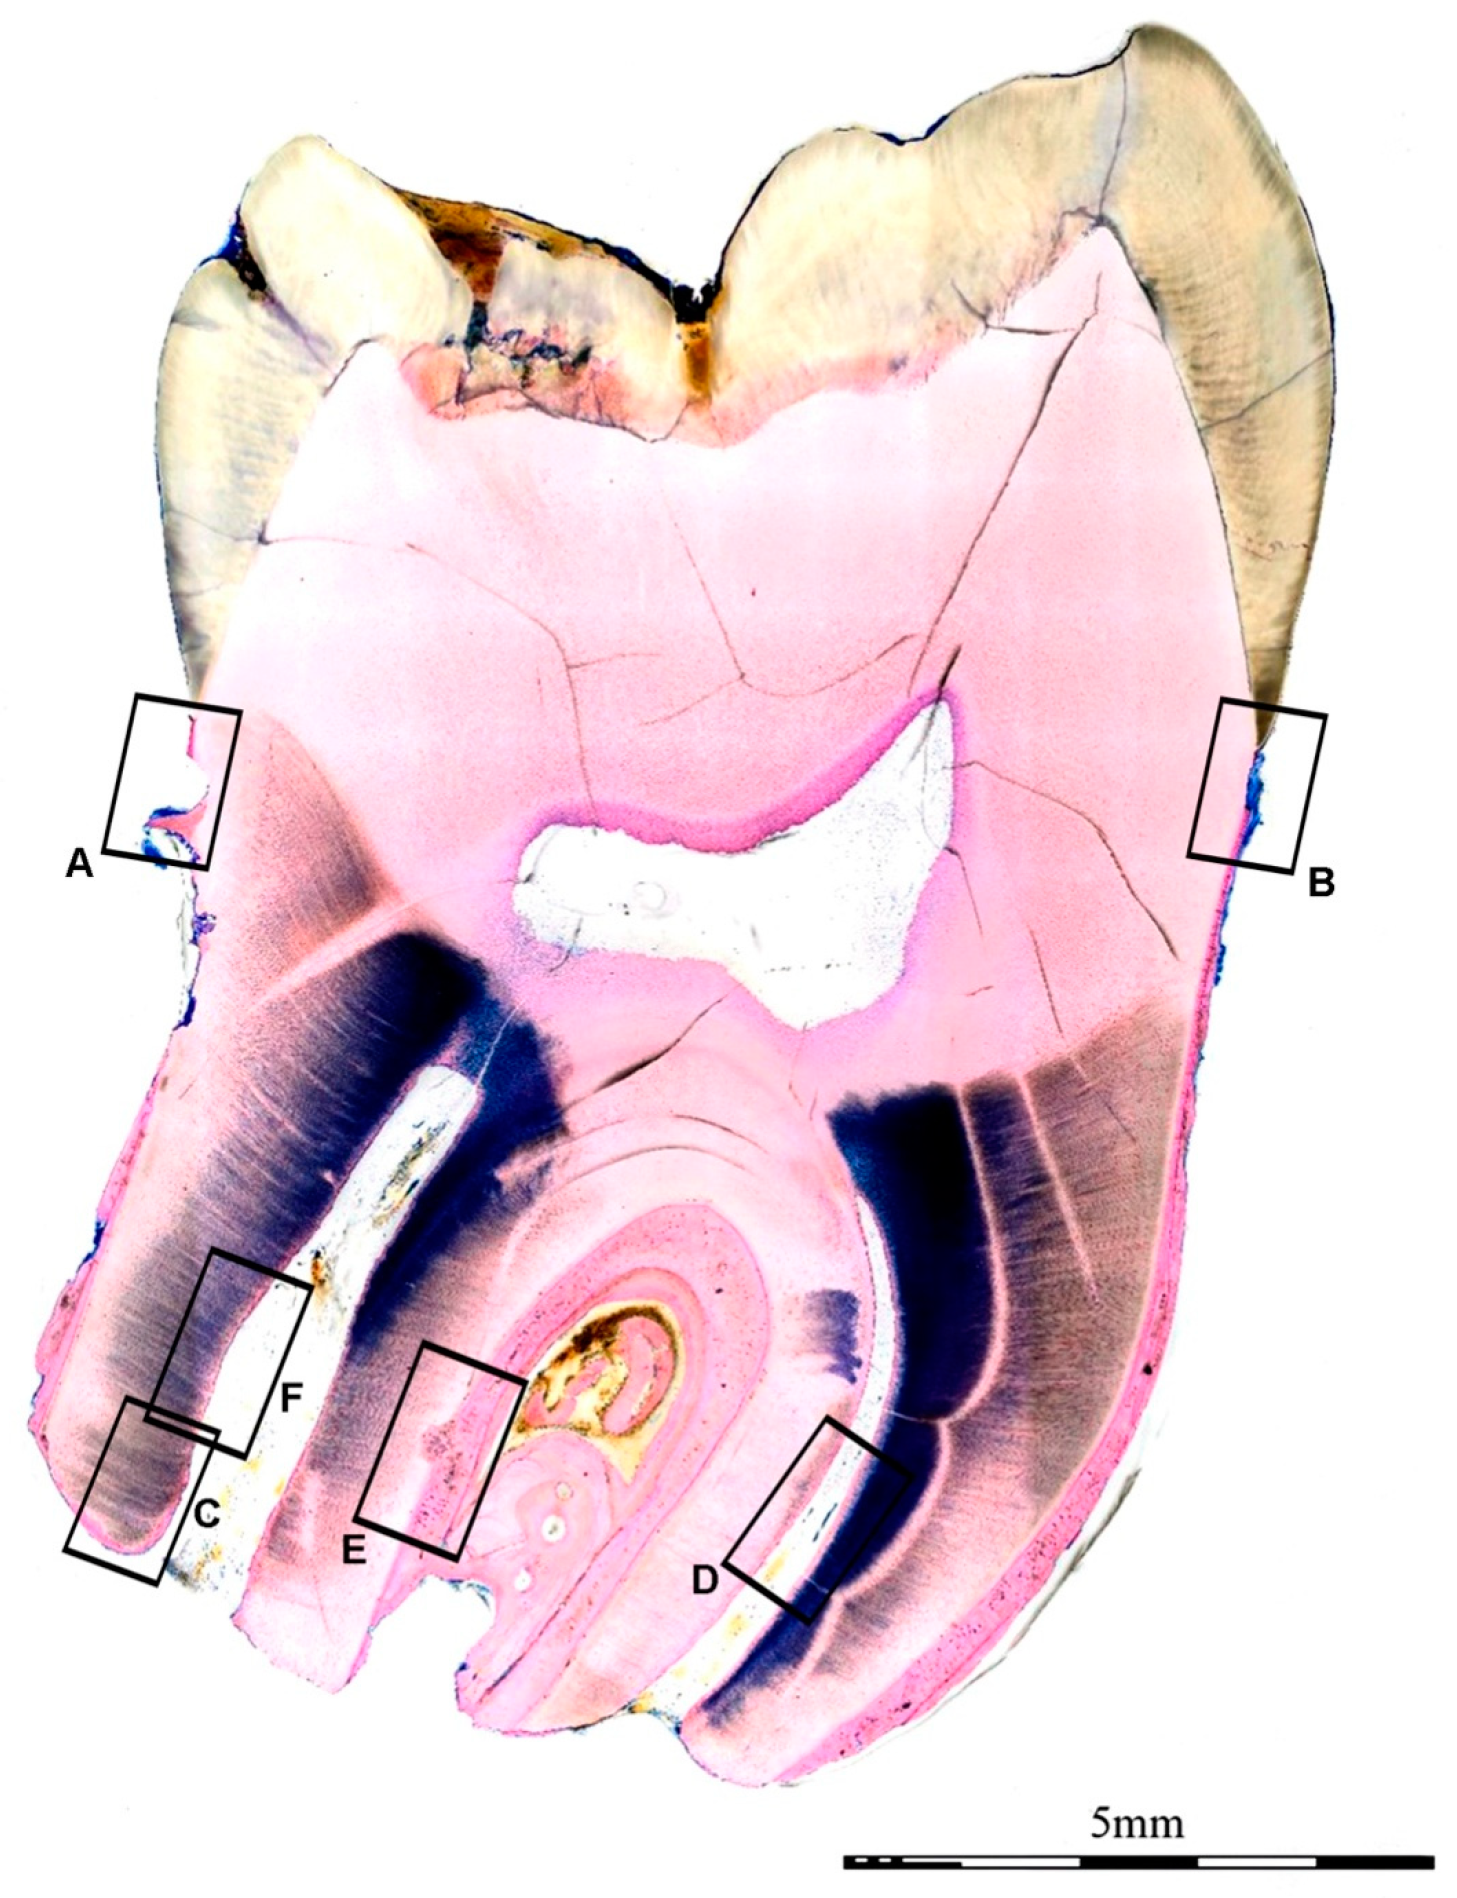

2. Report